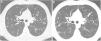

Of the total 83 patients evaluated at the CF clinical unit from 2007 to 2018, 64 (33 males) finally met the inclusion criteria; median age was 26.84 (SD 7.92) years. Demographic, clinical, microbiological and spirometric characteristics of the study cohort are shown in Table 1. The median interval between the two CT studies was 3.88 (SD 1.59) years. The mean spirometric values of the patients showed dynamic lung volumes lower than those of the general population, both in absolute values and as percentages of the reference values. FEV1% was 71.78 (SD 19.39) at the time of the first CT, and 66.74 (SD 19.94) at the last CT. Mean FEV1% annual variation was (−1.30, SD 2.66), indicating decrease of respiratory function. In the last study, score was higher and the annual score change was positive for every item, except for air trapping in which these parameters were lower and negative, respectively. These results indicate worsening of anatomic status over time, except for air trapping. Annual changes of mucous plugging, parenchymal alterations and air trapping were the radiological parameters that correlated with exacerbation (r was 0.291, 0.317 and 0.251, respectively, p value<0.05). Evolution of mucous plugging correlated with FEV1% worsening (r=−0.253, p value <0.05). (Fig. 1 shows the evolution of mucus plugging). No statistically significant relationship was demonstrated between annual changes of bronchiectasis or peribronchial thickening and number of exacerbations, FEV1% variation, or antibiotic cycles. The interobserver and intraobserver agreements for the different items were respectively: for bronchiectasis (0.85 and 0.99), mucus plugging (0.73 and 0.82), peribronchial thickness (0.89 and 0.97), parenchymal alterations (0.80 and 1) and air trapping (0.73 and 0.97), p value<0.05.

(a, b) Example of the evolution of two consecutive axial CT images (a: CT axial image at the first CT and b: CT axial image at the last CT) of a patient with cystic fibrosis demostrating a progression of mucus plugging. Brody II subscore for mucus plugging at the first CT was 5 and at the last CT was 10. There was also a decline of FEV1% (FEV1% 1 was 79% and FEV1%-2 was 66%). CT: computed tomography. FEV1%-1: forced expiratory volume in 1 second at the first CT time. FEV1%-2: forced expiratory volume in 1 second at the first CT time.